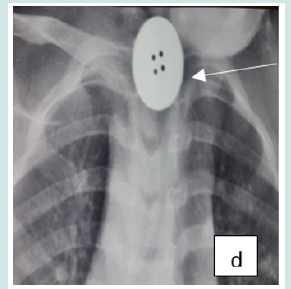

Cervico-thoracic X-ray performed in 211 cases (99%) showed opacity in 209 cases (99%). In one case, 2 circular opacities were observed, one of which had a double contour, indicating the ingestion of 2 foreign bodies (Figure 1: a, b, c, d, e, f). Foreign objects were a coin in 182 cases (85.4%), a shirt button in 4 cases (1.88%), a food in 7 cases (3.27%), and a flat battery in 3 cases (1.41%) (Table III). In 2 cases (1%) the EC was radiolucent.

Figure 1: Front cervico-thoracic radiograph showing different radiopaque foreign bodies (a,b,c,d,e,f). a: Circular esophageal CE of metallic tone, round opacity (coin).